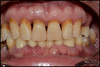

Avant: Gencive Enflammée

Après: Gencive dégonflée et stabilisée

après 6 semaines de brossage